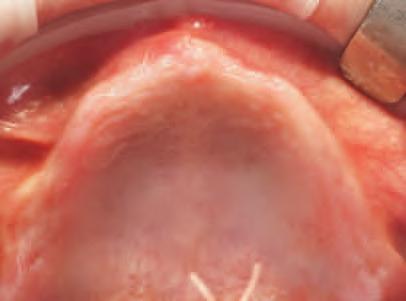

Implantur le subper ostale sunt structur metal ce fabr cate nd vdual pentru a se adapta ș a restab l zonele edentate. Personal zate ș concepute pentru a se potr v morfolog e osoase un ce a pac entulu , mplantur le subper ostale sunt plasate sub per ost ș sunt stab l zate pr n șurubur de f xare care ntră în contact cu osul sub acent ș țesutul f bros care le acoperă. Spre deoseb re de mplantur le convenț onale, mplantur le subper ostale se sprj nă d rect pe os ș prez ntă bontur care emerg pr n țesutur le g ng vale pentru a acomoda proteze f xe sau detașab le totale sau parț ale (un exemplu de implant subperiostal individualizat este ilustrat în fig. 6-14)

În z ua nserăr , după ce s-a real zat o expunere suf c entă a suportur lor anatom ce sub acente, mplantul este ver f cat în pr v nța adaptăr corecte, ar or ce mod f căr necesare sunt efectuate îna nte de plasarea f nală. Implantul este stab l zat pe poz ț e cu șurubur monocort cale nserate pr n găur predef n te în osul sub acent. Lamboul este decolat ș d secat corespunzător pentru a obț ne suf c entă pas v tate care să as gure o înch dere pr n ntenț e prmară în jurul bontur lor expuse ale mplantur lor. După per oada necesară de v ndecare, se au amprentele corespunzătoare pentru fabr carea ș l vrarea proteze f nale.